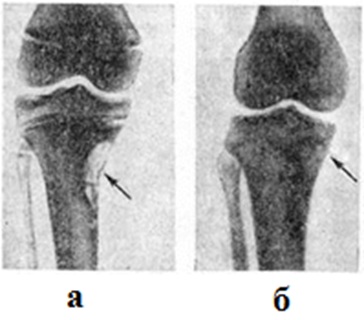

Фиброзный кортикальный дефект появляется в постнатальном периоде и бывает связан с повышенной статикофункциональной нагрузкой на определённый сегмент кости. Развитие фиброзных кортикальных дефектов характерно для детей со статико-функциональными нарушениями опорно-двигательного аппарата (сколиоз, плоскостопие, варусная и вальгусная деформация коленных и тазобедренных суставов и другие). Фиброзный кортикальный дефект проявляется развитием локальной зоны дегенеративно-дистрофической перестройки обычно в метафизарных отделах длинных трубчатых костей, у мест прикрепления связок и сухожилий. Очаг может быть одиночным, но нередко очаги возникают одновременно или последовательно в нескольких костях (например, на медиальной поверхности дистального метафиза бедра и медиально-задней поверхности большеберцовой кости). Возможно развитие фиброзных кортикальных дефектов в костях разных конечностей. Значительно реже очаги выявляются в субпериостальных отделах седалищной кости, лопатки и ключицы. Микроскопически очаг поражения представлен пучками коллагеновых волокон и вытянутых клеток фибробластического типа, среди которых можно встретить многоядерные гигантские формы. Для клинические, картины фиброзного кортикального дефекта характерно медленное нарастание локальных болей и ограниченная припухлость мягких тканей. Нередко патологический процесс протекает бессимптомно, а очаги поражения обнаруживают случайно, при проведении рентгенологическое исследований по другому поводу. Рентгенологические исследование почти всегда позволяет поставить правильный диагноз. Наблюдается характерное метафизарное расположение очагов. Очаги никогда не распространяются через зону метаэпифизарного росткового хряща на эпифиз. Фиброзный кортикальный дефект располагается в толще коркового слоя субпериостально и является краеобразующим. Он имеет сравнительно правильную овоидную или округлоовальную форму и всегда локализуется вдоль оси кости. Возможно истончение и незначительное вздутие прилежащего участка коркового слоя. Очертания кортикального дефекта чёткие, ровные или полициклические, фестончатые. Чаще всего структура очага равномерно прозрачная, иногда мелко или крупноячеистая. Со стороны прилежащих отделов очаг отграничен ободком остеосклероза (рисунок 6). Иногда на уровне кортикального дефекта определяется поперечно-расположенная лоозеровская зона (смотри полный свод знаний Лоозера зоны). Яффе (Н. L. Jaffe) и Л.. Лихтенстайн расценивают фиброзный кортикальный дефект как изолированную форму фиброзной Остеодисплазия, которая подвергается самопроизвольному обратному развитию или стабилизируется, но в отдельных случаях может переходить в опухолевый процесс. Для фиброзных кортикальных дефектов характерно самопроизвольное излечение, которое обычно наступает через 1½—2 года (рисунок 7). При более длительном восстановлении костной структуры показана краевая резекция поражённой кости. Фиброзные кортикальные дефекты следует дифференцировать с туберкулёзным оститом (смотри полный свод знаний Туберкулёз нелёгочный, туберкулёз костей и суставов), хондромиксоидной фибромой (смотри полный свод знаний), эозинофильной гранулемой костей (смотри полный свод знаний), изолированной кистой кости, остеоид-остеомой (смотри полный свод знаний), кортикальным абсцессом Броди (смотри полный свод знаний Броди абсцесс), остеобластокластомой (смотри полный свод знаний) и фиброзной остеодисплазией (смотри полный свод знаний).